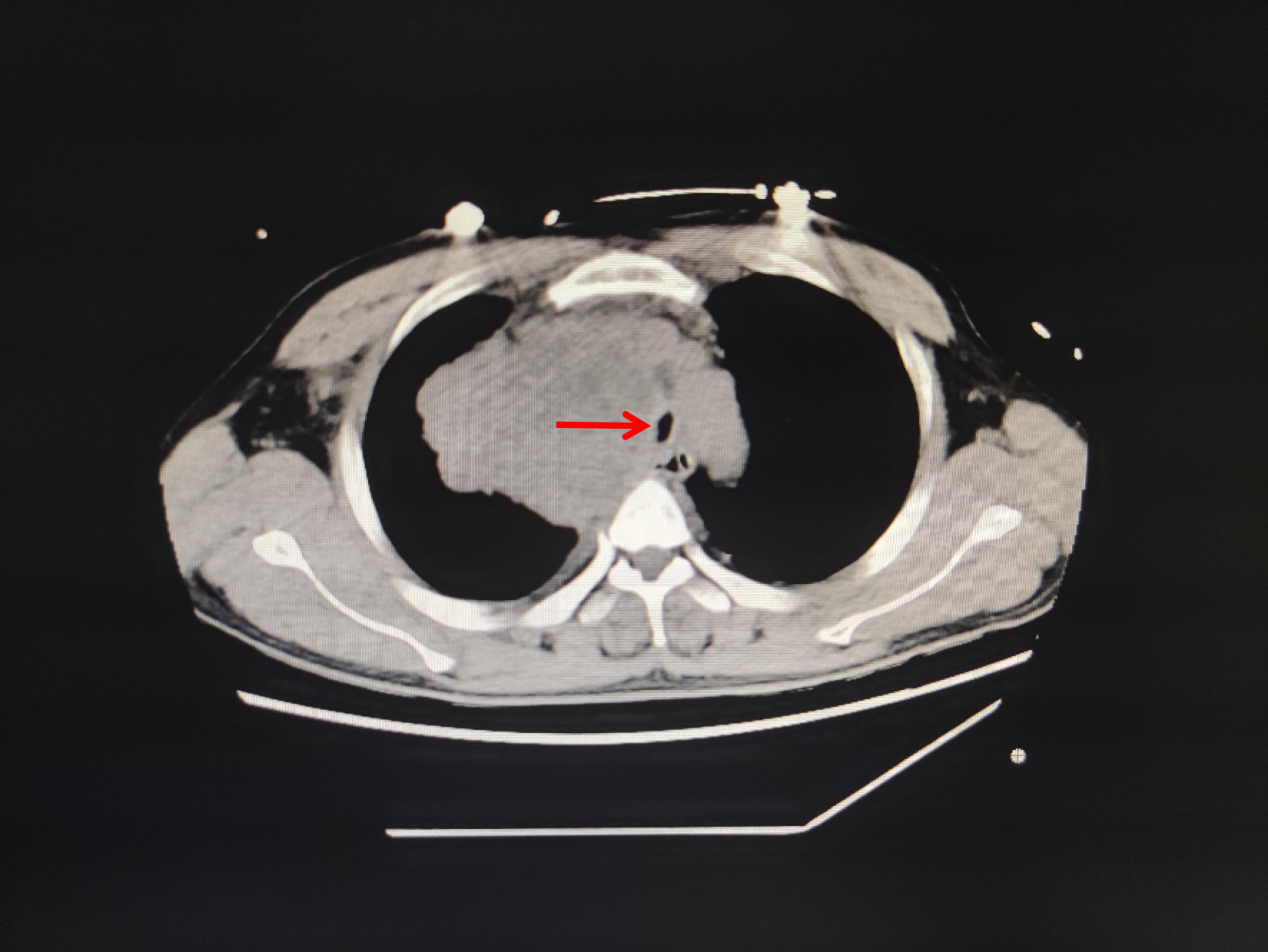

今年57岁的蔡女士,因晚期肺癌住院,肿瘤压迫气管导致气管严重狭窄,住院期间突发呼吸困难,伴烦躁不安、大汗淋漓,紧急行气管插管接呼吸机辅助通气,送ICU抢救。无独有偶,这边ICU医生正在积极抢救蔡女士,那边医院急诊科又打电话说急诊室有一名呼吸困难的患者需要紧急插管。这也是一名肿瘤压迫气管导致气管狭窄的患者,胸部CT可见气管中下段显著性狭窄,患者呼吸困难已近1周,今天突然加重,喘憋、口唇紫绀,ICU翁医生马上紧急予以气管插管,呼吸机持续性辅助通气。

图1.林某某CT 图2.蔡某某CT图片